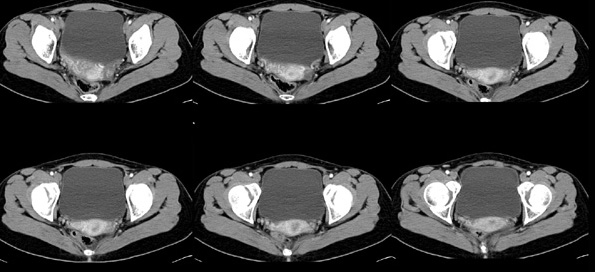

女性,28岁,停经3月,腹部膨隆1月,产前检查发现腹部占位

{肿块中心ct值27hu,增强后,动脉期、门脉期均无明显强化)

患者手术病理:腹腔囊性淋巴管瘤,象这样充满整个腹腔的的确很少见